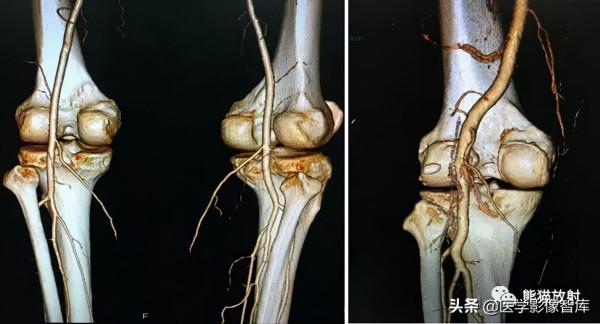

下肢CTA